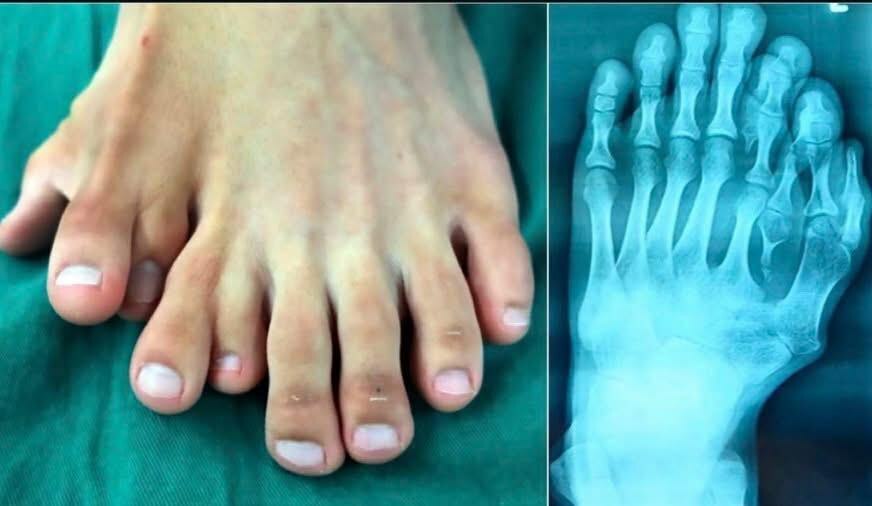

foot with many toes